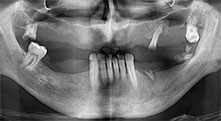

Professor Dr. Dr. Emanuel Bratu, maxillofacial surgeon, oral surgeon and prostheticist, is head of the implantology departments at two Romanian universities. He runs a renowned private hospital in Timisoara and is an internationally known researcher. In the interview Bratu explains why he considers that the W&H Piezomed piezosurgical device, and particularly two patented saws, have become essential for bone surgery.

Bratu: We routinely use the instruments for harvesting bone blocks and splitting alveolar ridges. We also use the Piezomed B6/B7 for osteotomy of impacted teeth and removing failed implants. All indications that require deep, clean cuts.

Bratu: We prefer to harvest bone from the external oblique ridge of the posterior mandible, not from the interforaminal region. After the soft-tissue incision, we use the new saws to define the amount of bone to harvest. With this approach, we also use them for the entire preparation in almost 80% of cases. We may also use other piezo instruments and then at the end a chisel to mobilize the block. We find that this is a very effective surgical technique.

Bratu: I consider piezo surgery a great leap forward in oral surgery. The technique makes bone preparation safer and easier. Little bone is lost, for example in extractions. This is very important in the aesthetic zone, particularly if immediate implantation is planned. Piezo surgery is also safer for soft tissue: injuries to membranes in the sinus are basically history, as are nerve injuries when bone blocks are being harvested. Data indicating reduced postoperative swelling and pain are also available. Piezo surgery is also ideal for preparation of sinus septa. And last but not least, our patients benefit from the atraumatic nature of this technology.